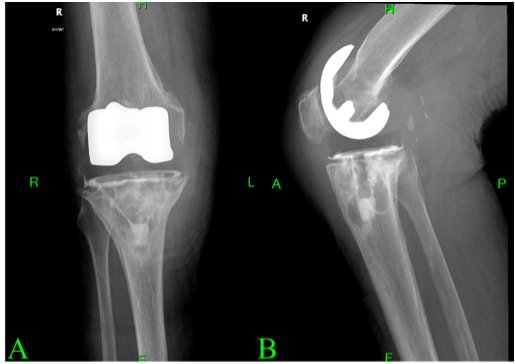

Therefore, 4 months after the onset of her symptoms. In October, the patient presented to the emergency department, where deep vein thrombosis was ruled out. She was diagnosed with erysipelas and started on oral clindamycin. As her symptoms persisted, she was re-evaluated in the orthopedic outpatient clinic, where joint aspiration was performed. The result was negative, leading to a preliminary diagnosis of aseptic loosening. She was subsequently referred to our department in November 2024, where a diagnosis of polyethylene wear was considered. Radiographs taken at that time (Fig. 2) revealed lytic lesions and significant bone resorption around both the femoral and tibial components.

Figure 2: Prominent resorptive changes are observed of the femoral component. Lytic lesions are also noted along the tray of the tibial component. The image in panel A (a) shows an anteroposterior view, while panel B (b) presents a lateral view of the radiograph.